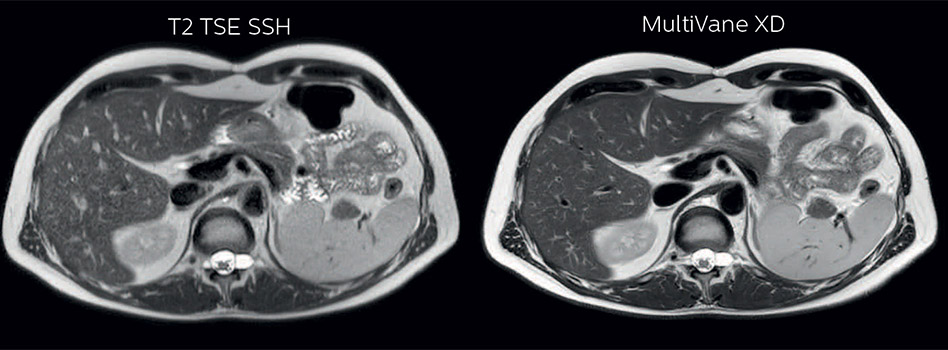

Comparison of liver MRI with and without MultiVane XD motion correction

In this example the image quality of the MultiVane XD images is evidently better than in the images without MultiVane XD. Ingenia 1.5T with dS Torso coil solution.